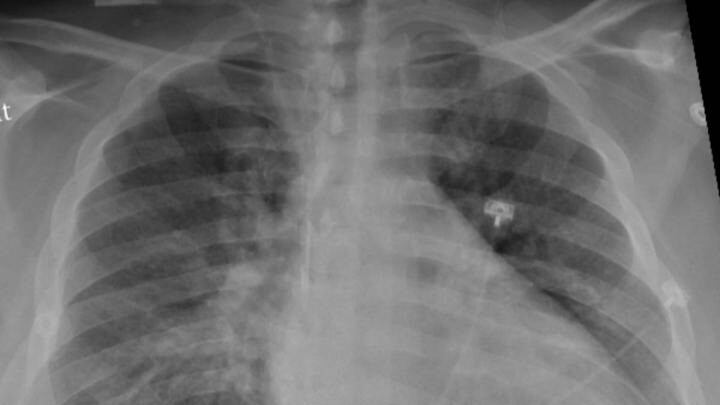

Las infecciones por covid-19 pueden provocar graves inflamaciones del pulmón y la formación de tejido cicatricial (fibrosis). Esto puede repercutir a largo plazo en la función pulmonar y es una de las causas del covid persistente.

En los pacientes de covid, unas células inmunitarias llamadas macrófagos desempeñan un papel importante en las infecciones inflamatorias graves y los daños pulmonares. Sin embargo, cuando el nuevo fármaco bloqueó la molécula de microARN de los macrófagos en ratones, se produjo una reducción significativa de la inflamación y el daño pulmonar y una mejora considerable de la función pulmonar.